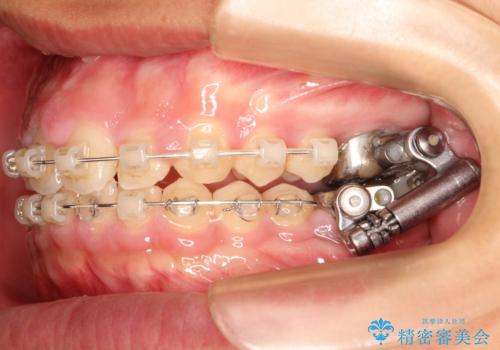

- 矯正装置

- インビザライン

インビザライン中のホワイトニングについて

基本的に矯正中であってもホワイトニング自体は施術可能です。

マウスピース矯正用のマウスピースは、ご自宅で行うホームホワイトニング用のトレーとしてご利用いただくことができます。

※インビザライン治療の場合ホワイトニングを行う前歯にアタッチメントと呼ばれるポッチを歯の表面に付けることがあるため、アタッチメントがついた状態でホワイトニングを行うことはオススメしておりません。